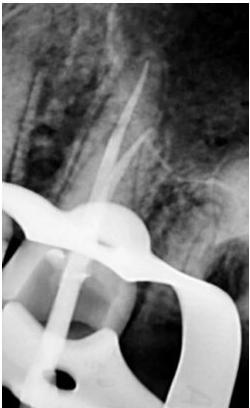

Case 1: 46 years old Male patient, ASA 1, presented for the evaluation and the treatment of tooth #36. On clinical examination the tooth was sensitive to percussion and palpation. The radiographic examination showed a very large radiolucency on both mesial and distal roots, a separated instrument in the mesio-lingual canal. The diagnosis of previously initiated with symptomatic apical periodontitis was made, and the endodontic treatment was indicated.

Following aesthesia and rubber dam placement, access was performed, and canals were located. The coreonal fragment was removed and the apical fragment was bypassed. The canals were instrumented using Edge endo X7 files (EdgeEndo) to size 35.04 in the mesial canals and 40.04 in the distal canal.

Canals were obturated using hydraulic condensation using EdgeBioCeramic Sealer (EdgeEndo). Bioceramic cement was used for its antibacterial and bioactive properties. The one year follow up shows a complete healing of the lesion.